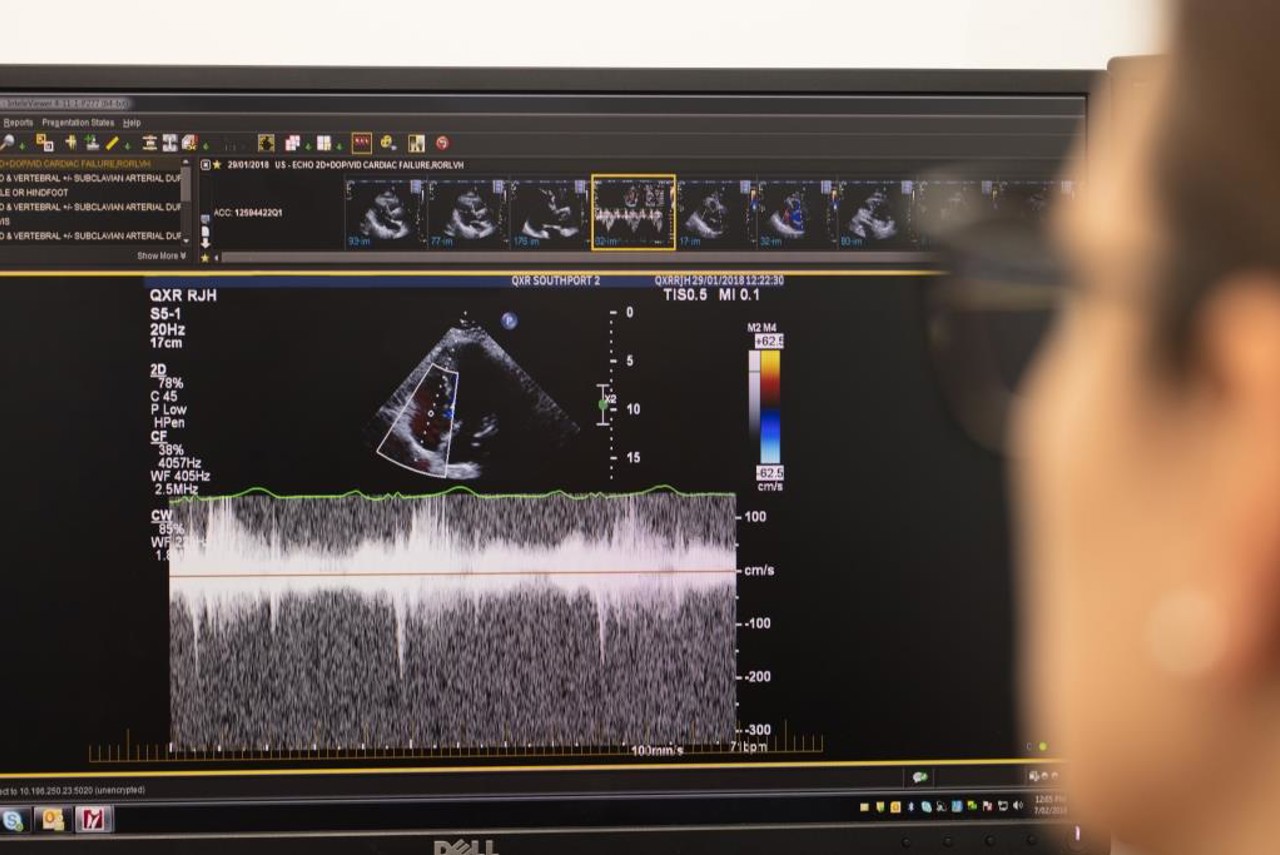

An echocardiogram or cardiac ultrasound provides important information needed to diagnose and manage heart conditions.

This scan can assess the size of the heart chambers, wall thickness, heart muscle function, progression of heart disease, valve function, masses in the heart, fluid around the heart, holes or defects, and abnormalities of blood flow within the heart. It can help diagnose atherosclerosis, cardiomyopathy, congenital heart disease, and cardiac tumours.